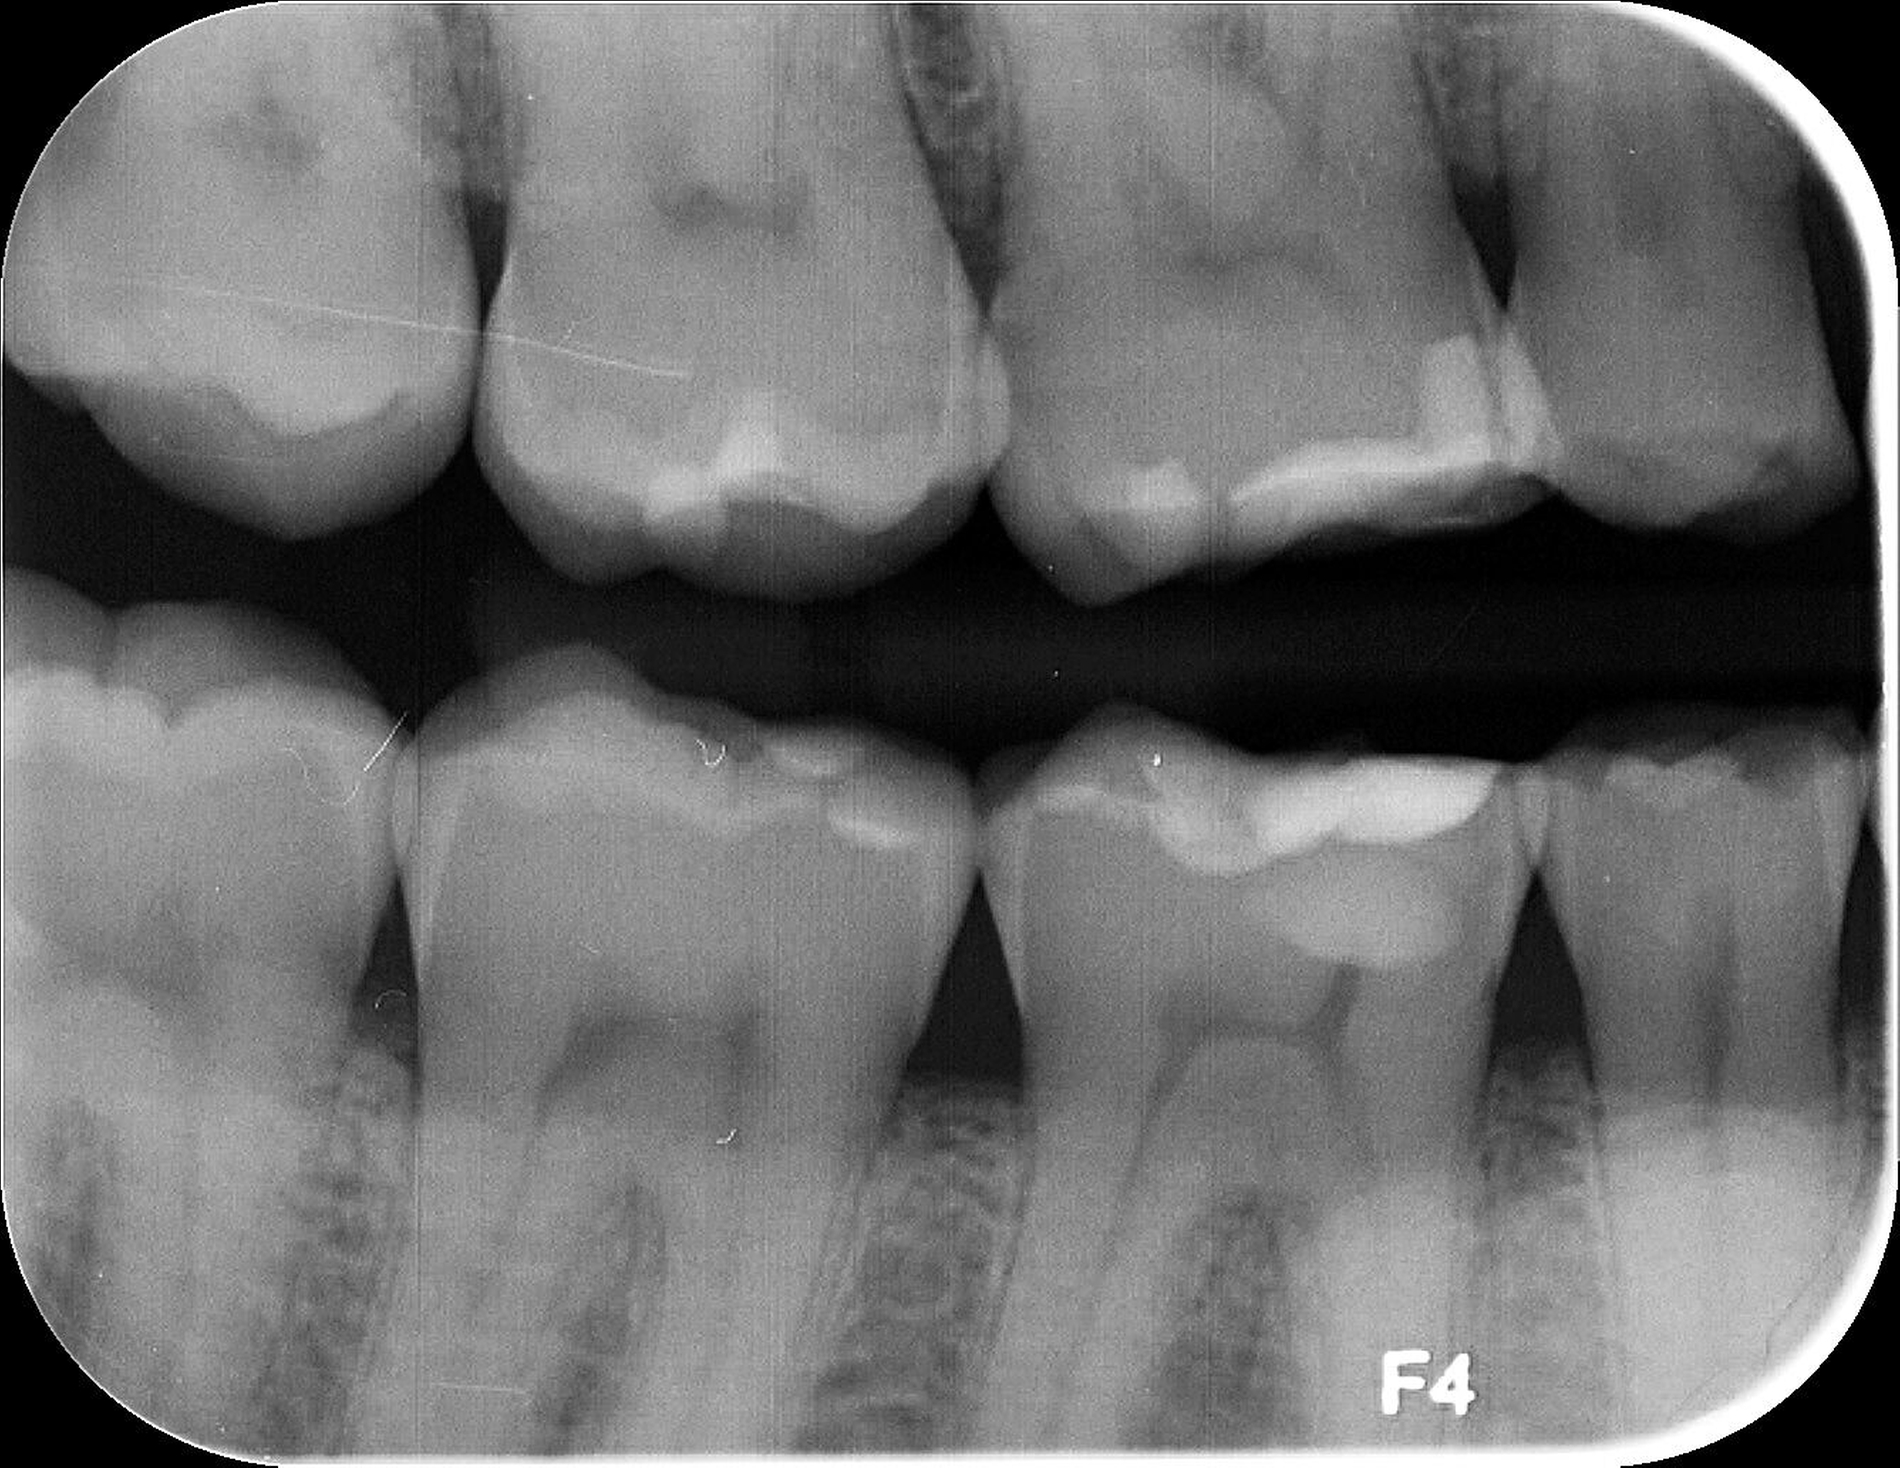

Das unter Beteiligung des Autors entwickelte Tooth Wear Evaluation System (TWES) 2.0 [Wetselaar et al., 2020] identifiziert per Screening Patienten mit erhöhten Verschleißwerten, vergleichbar mit dem PSI in der Parodontologie oder dem CMD-Kurzbefund. Bei auffälligen Werten folgt ein differenzierter Zahnverschleiß-Status einschließlich der Erfassung oraler und vestibulärer Substanzverluste [Wetselaar et al., 2016 sowie von Pathologie-Symptomen und einer strukturierten Diagnose [Tonetti und Sanz, 2019; Wetselaar, 2020]. Den Einsatz in der Praxis illustriert der in den Abbildungen beschriebene Patientenfall aus dem CMD-Centrum Hamburg-Eppendorf.

Zahnverschleiß-Status

Im Unterschied zum Zahnverschleiß-Screening wertet der Zahnverschleiß-Status den höchsten Verschleißgrad pro Zahn aus, und zwar okklusal/inzisal, oral und vestibulär (Abbildungen 4b und 4c, Tabelle 1). Wichtig für die Planung therapeutischer Maßnahmen ist die Frage, welche Zähne okklusal in Kontakt stehen, denn die Behandlung von Zähnen mit erheblichem Zahnverschleiß lässt keinen weiteren Substanzverlust zu und erfordert bei Zähnen in Kontakt absehbar eine Erhöhung der vertikalen Dimension der Okklusion.

Der Zahnverschleiß-Status erfasst auch zehn Kriterien, die nach der Literatur Anzeichen eines pathologischen Geschehens sind. Als pathologisch wird Zahnverschleiß demnach eingeordnet, wenn bei Grad 3 zusätzlich mindestens ein Pathologie-Kriterium vorliegt (Abbildung 6).

Ergänzt wird der Zahnverschleiß-Status durch 20 Merkmale, die jeweils chemischen und mechanischen Ursachen zugeordnet sind und in der summativen Auswertung zeigen, welche Ursachen offensichtlich dem Geschehen zugrunde liegen. Dies ist auch bei vermeintlich eindeutigen Fällen hilfreich, da zuweilen mehrere Faktoren ineinandergreifen, die dann möglichst alle abzustellen sind, bei erheblichem oder extremem pathologischem Zahnverschleiß einhergehend mit einer eventuellen restaurativen Therapie.

Wichtig für das Therapiekonzept ist zudem der Umfang des Zahnverschleißes. Die Auswertung unterscheidet daher lokalisierten und generalisierten Zahnverschleiß.

Im Beispiel ist daher die Diagnose ein generalisierter erheblicher und lokalisierter moderater pathologischer Zahnverschleiß überwiegend mechanischer und zudem chemischer Ursache. Die sich daraus ableitende Erkenntnis ist, dass in allen Sextanten Zähne freiliegende Dentinkerne aufweisen (generalisierter moderater Zahnverschleiß), dass darüber hinaus Zähne erheblich geschädigt und somit gefährdet sind, dass Merkmale eines pathologischen Geschehens bestehen – und dass als Ursache neben dem dominierenden Bruxismus ein Säureeinfluss hinzukommt.

Auch wenn Restaurationen nach Möglichkeit vermieden werden sollten, ist deren Verfügbarkeit für die Betroffenen individuell höchst wichtig, weil sie bestehende Schmerzen beseitigt, die verlorengegangene Kauleistung wiederherstellt und ästhetische und nicht zuletzt auch phonetische Einschränkungen aufhebt. Bei dem in den Abbildungen beschriebenen Fall korrelierte der erhebliche Zahnverschleiß mit der Lokalisation der Zahnschmerzen des Patienten. Direkte Restaurationen mit Kompositen hatten keinen Bestand. Die durchgeführte restaurative Behandlung hingegen hat Bestand, die Schmerzen waren danach umgehend verschwunden und sind seit zehn Jahren nicht wiedergekehrt.